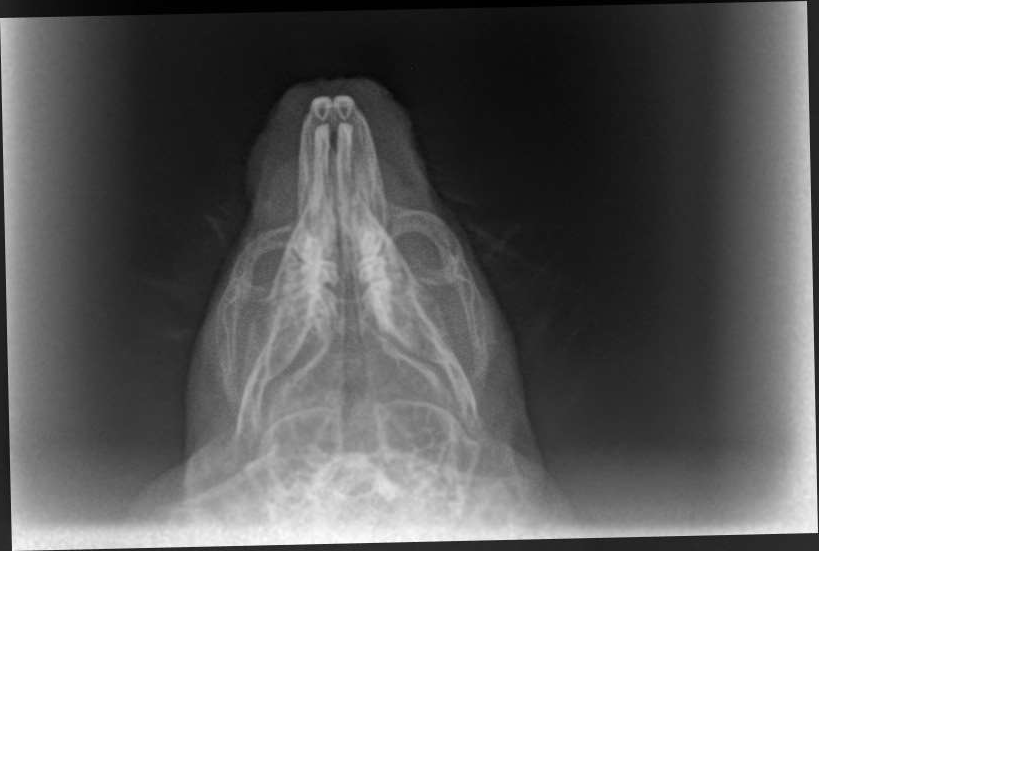

Zum Vergleich eines von Diabolo LG